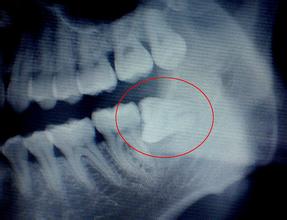

很多人長智齒時,會出現(xiàn)智齒萌生不全、智齒阻生等情況的發(fā)生,引發(fā)疼痛等相關口腔問題的發(fā)生,更因其生長位置的特殊性,給其護理及清潔工作帶來極大的影響,因此及時將生長不良的智齒給予拔除是非常重要的。

關于拔智齒的危害,我們知道,拔牙的主要目的是將影響口腔及身體健康而無法通過治療保留的患牙給予拔除,智齒由于其生長時期及生長位置的特殊性,因此極易引發(fā)各類口腔及身體問題的發(fā)生,加上其他本身是一種多余、痕跡器官。因此很多情況下需進行拔智齒處理。

那么,拔智齒的危害有哪些呢,漳州衛(wèi)生職業(yè)學院附屬口腔醫(yī)院醫(yī)生指出:拔智齒本身是沒有危害的,將生長不良,影響口腔及身體健康的智齒拔除,不僅沒有危害,更可避各智齒帶來的各種后遺癥的發(fā)生。而如果不將生長不良的智齒給予拔除,其可帶來以下方面的危害:

首先:位置不正的智齒與第二磨牙之間容易積存食物殘渣,而且不易清潔,一般數(shù)月可形成齲齒,直接破壞牙體組織。

其次:阻生的智齒往往不能與對頜牙齒建立正常的咬合關系,長時間可導致顳下頜關節(jié)彈響、張口疼痛,夜磨牙等癥狀,對輕壯年的身心健康影響較大。

再次:阻生的智齒牙冠周圍軟組織與牙齒之間形成一盲袋,引起食物、細菌的積存,抵抗力下降時,出現(xiàn)冠周炎是必然的。一般的消炎治療治標不治本,因此冠周炎會反復發(fā)作。